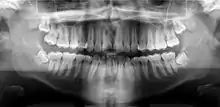

![]() A dental panoramic radiograph, showing the maxilla and mandible, all the teeth including the "wisdom teeth," the frontal and maxillary sinuses, the nasal cavity and the temporomandibular joint and other near by head and neck anatomy. | |

A panoramic radiograph is a panoramic scanning dental X-ray of the upper and lower jaw. It shows a two-dimensional view of a half-circle from ear to ear. Panoramic radiography is a form of focal plane tomography; thus, images of multiple planes are taken to make up the composite panoramic image, where the maxilla and mandible are in the focal trough and the structures that are superficial and deep to the trough are blurred.